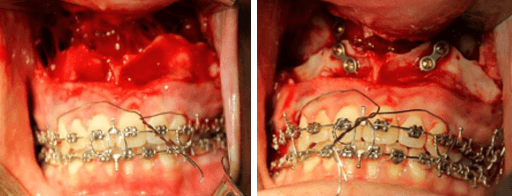

Condilectomia Alta

Osteotomía Le Fort I y Genioplastia